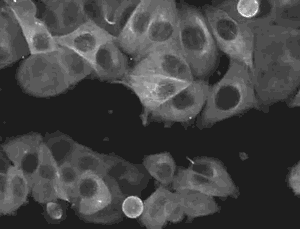

间充质干细胞,又称多潜能基质细胞,简称MSCs,是属于中胚层的一类多能干细胞,主要存在于结缔组织和器官间质中。在适宜条件下可分化为脂肪、骨、软骨等多种组织细胞。间充质干细胞的特性:

在这之中,有一种人体细胞最受到关注,它是「间质干细胞」(mesenchymal stem cells,MSC)。